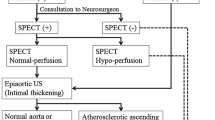

We, therefore, investigated whether it might be possible to narrow down cases with a high likelihood of hyperperfusion after carotid endarterectomy (CEA) or carotid artery stenting (CAS)—in other words, those truly needing confirmation of CVR with acetazolamide-challenge SPECT—by screening for the presence of escape routes by preoperative MR angiography with or without plain SPECT.

Ogasawara et al. [14] reported that patients with postoperative hyperperfusion often featured a low vascular reserve, while Hosoda et al. [6] attached significance to baseline rCBF reduction for prediction of hyperperfusion. Not all patients, however, need investigation for CVR to predict hyperperfusion—especially considering the frequency of the event, the potential side effects of acetazolamide [17] and the medical costs of the procedure. Therefore, to avoid unessential examinations, cases with poor escape routes (Group P) are recommended to be selected by MR angiography first and then undergo further rCBF study with acetazolamide challenge to confirm the vascular reserve as designated in this study.

Patients in whom poor escape routes were observed (Group P) in preoperative MR angiography occupied one fourth of all cases. In our series, all four cases with hyperemia or hyperperfusion belonged to this group. Among 17 Group P cases, 14 (82.4 %) showed Type I, which are thought to easily lead to hyperemia/hyperperfusion. So, patients with this group have higher risks for hyperemia/hyperperfusion. In the present study, the incidence of preoperatively depressed rCBF (more than 10 % compared to the contralateral side) was limited to only one in 17 in Group P cases (5.9 %). The preoperative depressions of rCBF of the two Group P hyperemia cases were small (5.0 and −0.5 %). These findings may suggest that a certain number of patients with hyperemia/hyperperfusion can be ascribed to the poor escape routes itself or cases with normal rCBF and decreased CVR. When patients with a decrease of rCBF and/or decreased CVR are added to the P-group cases, however, it is apparent that the possibility of CHS becomes greater, as previous researchers have described [5, 6, 14].

Therefore it can be argued that a CVR test with acetazolamide-challenge SPECT should be considered only in cases with poor escape routes (Group P). This would allow the narrowing down of candidates for drug-challenge SPECT to about one fourth of all patients. Where preoperative SPECT at rest is available, particular attention also should be paid to those few cases with good escape routes (Group G) having preoperatively depressed rCBF of the hemisphere of the ICA stenosis side. In most institutes, especially in small to medium-scale hospitals, post-CEA or CAS patients may be cared for in a general ward after the operation and if patients show severe headache or high BP in spite of ordinary BP treatment, strict systolic BP control under 100 using continuous drip infusion of nicardipine or diltiazem hydrochloride and ICU observation for sedation with thiopental or propofol [21]. We believe that our strategy using preoperative assessment of collateral pathways as escape routes would be useful to decide taking these advanced and aggressive measures to avoid CHS and also be cost-effective. It may be effective to decrease CHS cases with prophylactic administration of edaravon before carotid clamping in CEA for reduction of free radicals as pointed out by Ogasawara et al. [15] in suspected cases of hyperemia/hyperperfusion with poor escape routes.

Preoperative evaluation and detection of poor escape routes with postoperative concentration of blood flow because of reconstructed ICA by MR angiography is recommended before surgical treatment of carotid stenoses. This should limit the cases that really need investigation of CVR by acetazolamide-challenge SPECT. If plain SPECT at rest is also affordable preoperatively, a drug-challenge test for CVR is reasonable for the few cases with decreased rCBF and good escape routes, as well as for those with poor escape routes.